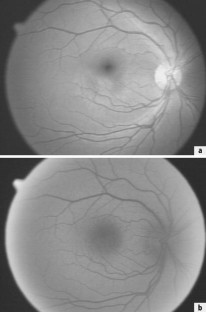

Abb. 2a,b.

An 18 gesunden Probanden (mittleres Alter: 23,9 Jahre) wurde die örtliche Verteilung der optischen Dichte proportionalen Xanthophyllkonzentration aus monochromatischen Fundusfotografien im blauen Spektralbereich sowie aus Autofluoreszenzaufnahmen bestimmt. Die Aussagefähigkeit der Parameter Gesamtkonzentration, maximale und mittlere Konzentration wurden verglichen.

Im Mittel über alle Probanden wurde in guter Übereinstimmung mit der Literatur eine maximale optische Dichte des Makulapigmentes von 0,29±0,08 aus den Reflexionsaufnahmen bestimmt. Zur Einschätzung des globalen Xanthophyll-Status eines Patienten scheint jedoch die mit der Maximalkonzentration korrelierende Gesamtkonzentration geeigneter zu sein. Die geringe Intensität der Autofluoreszenzaufnahmen lässt diese als zur Bestimmung der Xanthophyllkonzentration weniger geeignet erscheinen.

The local distribution of xanthophyll density was determined from monochromatic blue reflection images and autofluorescence images of the fundus in 18 healthy volunteers (mean age: 23.9 years). The significance of the parameters maximal, global, and mean concentration were compared.

The maximal optical density of xanthophyll determined from reflection images was found to be 0.29±0.08 (mean for all test persons) which is in good agreement with literature data. The total xanthophyll concentration which is proportional to the maximal density, appeared to be appropriate to describe a person's overall xanthophyll status. Because of the low intensity of autofluorescence images, these are less useful for the determination of the xanthophyll concentration.